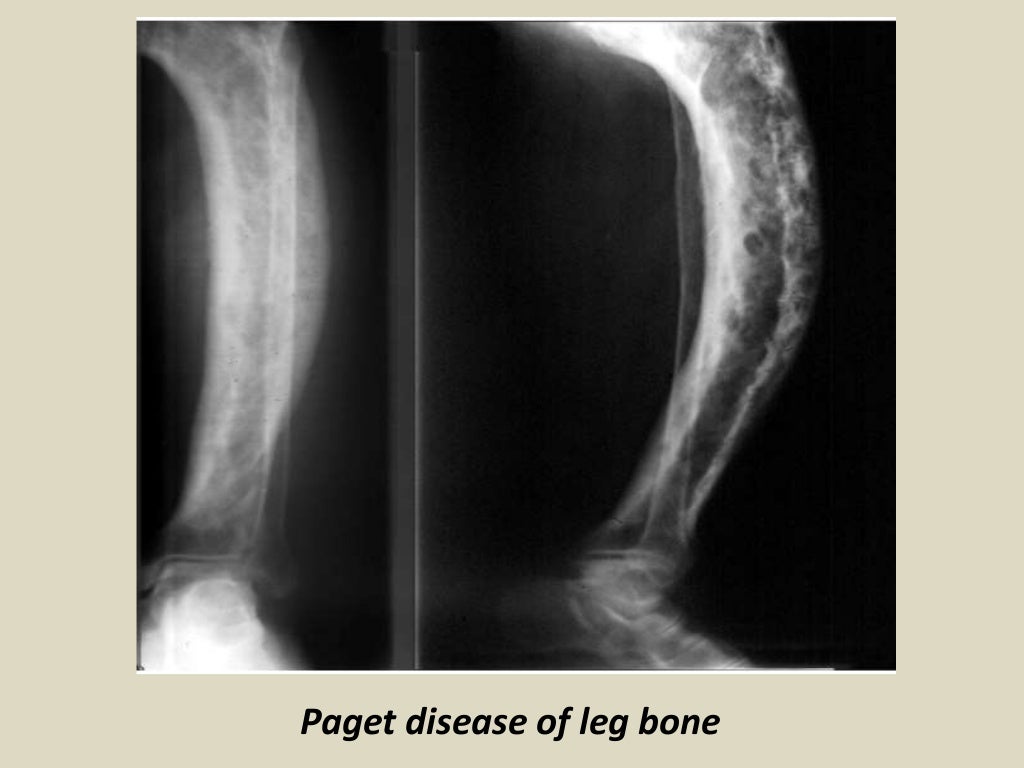

Presentation1.pptx, radiological imaging of paget disease. Juvenile Paget's Disease Radiology juvenile paget’s disease (jpd), an autosomal recessive disorder, manifests extremely fast skeletal remodeling, and is. juvenile paget’s disease (jpd) is a rare, generalized skeletal disorder characterized by markedly increased bone. juvenile paget's disease, also called hyperostosis corticalis deformans juvenilis or hereditary hyperphosphatasia (number 239000 in mendelian inheritance in man [mim]), 1 is a rare,. familial idiopathic. Juvenile Paget's Disease Radiology.